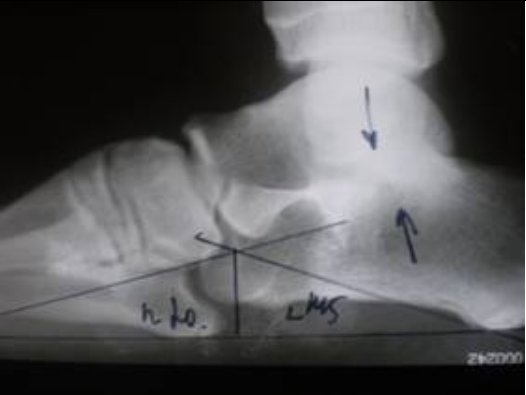

Рентгенологические изменения при данной патологии можно увидеть на фото ниже.

— через 2 нед от начала болей в диафизе II плюсневой кости тонкая линия, напоминающая перелом («маршевый»);

— через 2 мес, диафиз утолщен за счет периостальных наслоений на уровне поперечной зоны перестройки.

Снимки после соответствующей «обработки».

ОЧЕНЬ, НУ ОЧЕНЬ ИНТЕРЕСНЫЙ СЛУЧАЙ. А почему Вы думаете о болезни Дейчлендера или о так называемой «патологической зоне перестройки»?

Мне кажется что структурная перестройка 2й плюсневой кости характерна для данной болезни.

Диагноз выставляется на основании опроса, осмотра и данных рентгенографии. Решающее значение при этом имеет картина, полученная в ходе рентгенологического исследования. При болезни Дейчлендера в области диафиза пораженной плюсневой кости (иногда – ближе к головке, иногда – к основанию, в зависимости от локализации наиболее функционально перегруженного участка) выявляется изменение структурного рисунка. Определяется косая или поперечная полоса просветления (зона просветления Лоозера) – область перестройки кости. Выглядит так, как будто плюсневая кость разделена да два фрагмента. Однако, в отличие от рентгенологической картины при переломе, смещения в данном случае не наблюдается.

В последующем вокруг пораженного отдела кости возникают периостальные разрастания. Вначале они тонкие и нежные, затем – плотные, похожие на веретенообразную костную мозоль. Позже зона просветления исчезает, наступает склерозирование. С течением времени периостальные наслоения рассасываются. При этом кость навсегда остается утолщенной и уплотненной. Определяющими признаками являются отсутствие острой травмы, типичная локализация повреждения, а также наличие зоны перестройки при отсутствии смещения фрагментов и сохранении правильной формы кости. Следует учитывать, что в течение первых нескольких дней или недель рентгенологические признаки заболевания могут отсутствовать. Поэтому при характерных симптомах иногда требуется выполнить несколько рентгенограмм с определенным временным интервалом.

Снимки после соответствующей «обработки».

ОЧЕНЬ, НУ ОЧЕНЬ ИНТЕРЕСНЫЙ СЛУЧАЙ. А почему Вы думаете о болезни Дейчлендера или о так называемой «патологической зоне перестройки»?

Мне кажется что структурная перестройка 2й плюсневой кости характерна для данной болезни.